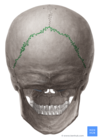

CORONAL SUTURE

LAMBDOID SUTURE

SAGITTAL SUTURE

SQUAMOUS SUTURE